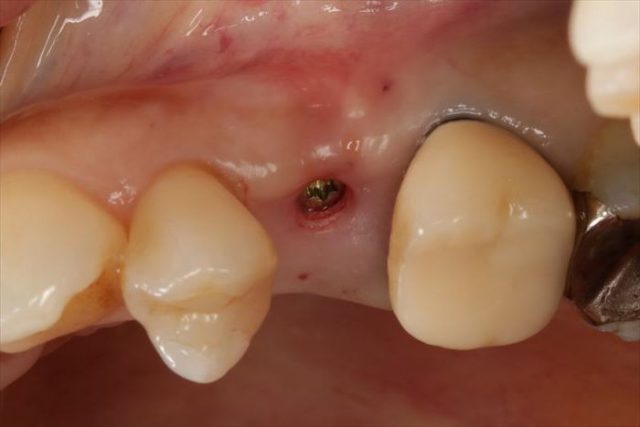

咬合面観です。

近遠心幅が狭いのでポジションの位置決めには緊張します。

封鎖スクリューでインプラントフィクスチャーを保護します。

フラップレス埋入オペでは出血もあまりありません。

無事に終わりました。